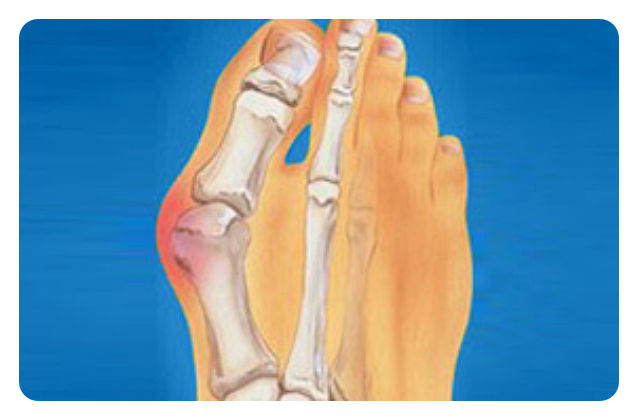

무지외반증은 엄지발가락이 두 번째 발가락 쪽으로 많이 휘고, 엄지발가락과 관절을 이루는 중족골이 안쪽으로 휘어진 형태입니다. 발생 원인은 평발이나 넓적한 발, 과도하게 유연한 발 등으로 생기기도 하며, 후천적으로 높은 굽의 신발이나 하이힐을 자주 사용하는 경우에도 생길 수 있습니다. 또한 유전적으로 발생하거나, 관절염으로 인해 합병증으로 발생하는 경우도 있습니다. 가장 흔히 나타나는 증상은 관절 안쪽의 통증입니다.

신발에 자극을 받아서 발가락이 두꺼워지면, 그 다음으로는 두 번째, 세 번째 발가락에도 영향을 주게 되며, 결국 피부 관절이 탈구되기도 합니다. 외형적 변형만 봐도 쉽게 진단할 수 있습니다. 하지만 치료 방향성을 결정하기 위해서는 방사선 찰영상 검사가 필요할 수 있습니다. 대부분 발에 체중이 실린 상태에서 찰영상을 진행하게 되고, 과학적으로 측정하여 관절의 변화를 관찰하게 됩니다. 의사는 엄지발가락의 관절 돌출 정도, 겹침 정보, 관절 자체의 통증 여부, 전체적인 관절의 유연성 여부 등을 검사하게 됩니다.